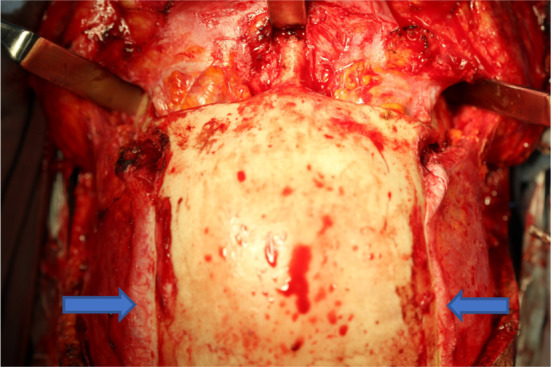

The MAZLFIIIO can be achieved through different surgical approaches, such as coronal, transconjunctival with Mustarde’s canthotomy or subcilliary with Mustarde’s canthotomy, also, intraorally through an extended vestibular incision. The ideal approach to avoid skin scars is the combination of the coronal approach with the transconjunctival approach. For the coronal approach, the dissection must have two fundamental principles, the first, the temporal’s dissection depth must be over the temporal fascia to avoid injuries to the frontal branch of the facial nerve. This cleavage plane is demonstrated by the blue arrows. The second principle consists in having a wide zygomatic dissection in order to be able to perform the osteotomies, such as the ones in (Fig. 5).

Fig. 5.

The coronal flap is extended up to the zygomatic bone and the temporal fasciae remain intact